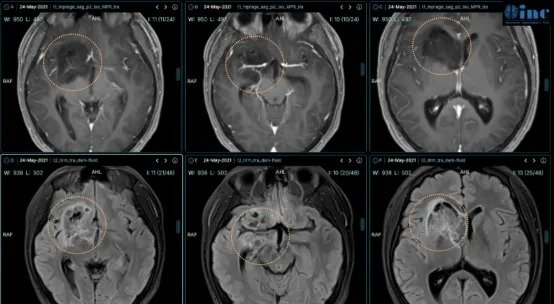

小磊术前MRI影像显示右额、颞、基底节区、侧脑室前角区巨大占位(胶质瘤),压迫丘脑,从右额白质延伸到岛叶和基底节前部,部分浸润丘脑和右下丘脑,并向颅内延伸到前连合和室间孔。

肿瘤血管丰富包裹大脑前动脉、大脑中动脉及其分支等。